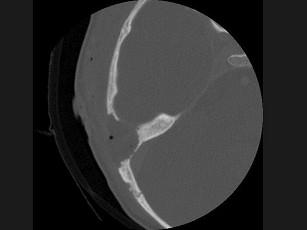

问题 女性,17岁,右耳乳突区隐痛,右耳后乳突区出现包块,逐渐增大,CT检查如图所示,请选择最可能的 ( )

选项 A、中耳癌 B、听神经瘤 C、化脓性中耳炎 D、嗜酸性肉芽肿 E、胆脂瘤

答案 D